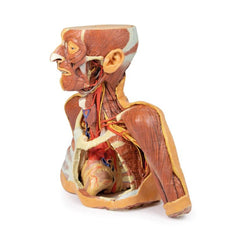

3D Printed Thoracic Cross Section at T6

This model is a cross-section of the thorax at the level of the T6 vertebra. Beginning posteromedially at the spinal

cord within the vertebral canal, then moving radially, the costovertebral joints of the 6th ribs are visible,

followed by several other ribs around the margin of the thoracic cavity, a pair of which unite anteriorly with the

sternum via the costosternal joints. Additionally, the oesophagus and descending aorta are visible anterior and

lateral to the T6 vertebral body, respectively.

Inside the plural space, lined by the parietal pleura,

reside the

inferior and middle lobes of the right lung and the inferior lobe of the left lung.

In the middle

mediastinum the

heart, within the pericardium, is transacted to reveal the left atrium posteriorly, then moving clockwise, the

aortic valve, right ventricle and the right atrium.